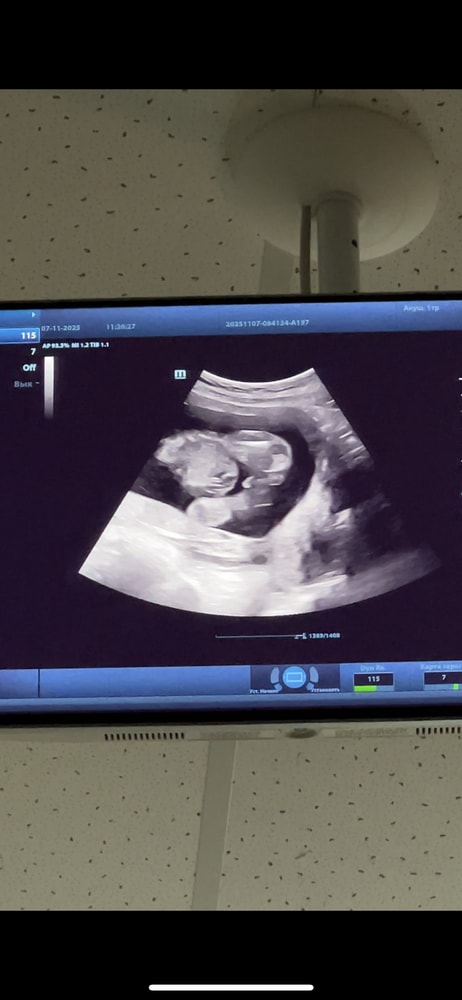

По первому фото я вообще понять ничего не могу . А вот тут оно самое ?😂 записалась еще на одно узи , через неделю. Уже не могу ждать ) или уже правда кровь сдать Изображение

Маша, по этому узи очень похоже что мальчик

Татьяна, у нас у мальчика. Прям пипка торчала, а тут как будто то ее нет

Libe, у нас тоже,помимо яичков пипка была,а на этом узи как будто просто яичники

Евгения, как будь-то "пирожочек" плохо прорисованный

Маша, я вижу девочку

Евгения, 😌 где? Я тоже хочу ее увидеть 😅 вот это тогда что 🙈 Изображение

Маша, яичники это,а у мальчиков помимо этого ещё пипка торчит)

Маша, пипка прям пипка, палочка.

Маша, примеры Изображение Примеры из интернета,мне кажется ваш случай девочка Изображение

Евгения, вообщем пойду еще на узи в другую клинику, посмотрим что там скажут 🙈

Изображение